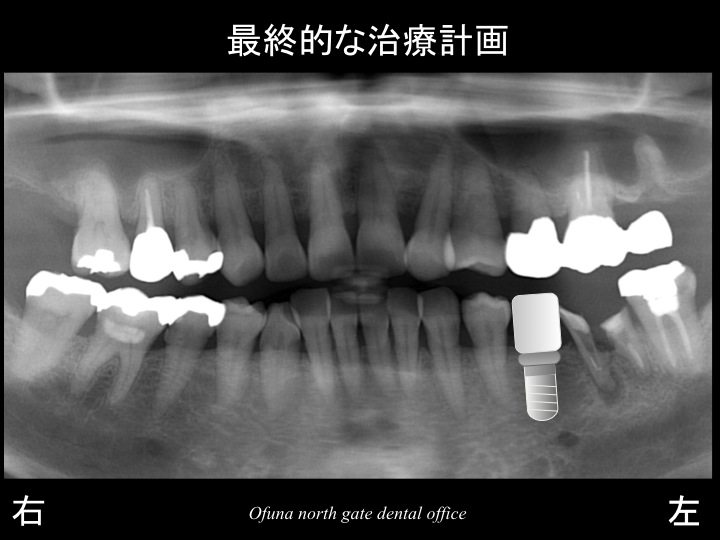

それでは、理想的な治療方法について解説します。

先程もご説明したように欠損部の奥の歯は、あまり良い状態とは言えません。

そのため、この歯は抜歯とした方が将来性は高いと言えます。

そして、インプラントを2本埋入するのです。

これが最も将来性が高い治療と言えます。

等をご説明した結果、患者様は欠損部にインプラント治療を行うことになりました。

これが治療計画というものです。

以下はインプラント治療が終了した後です。